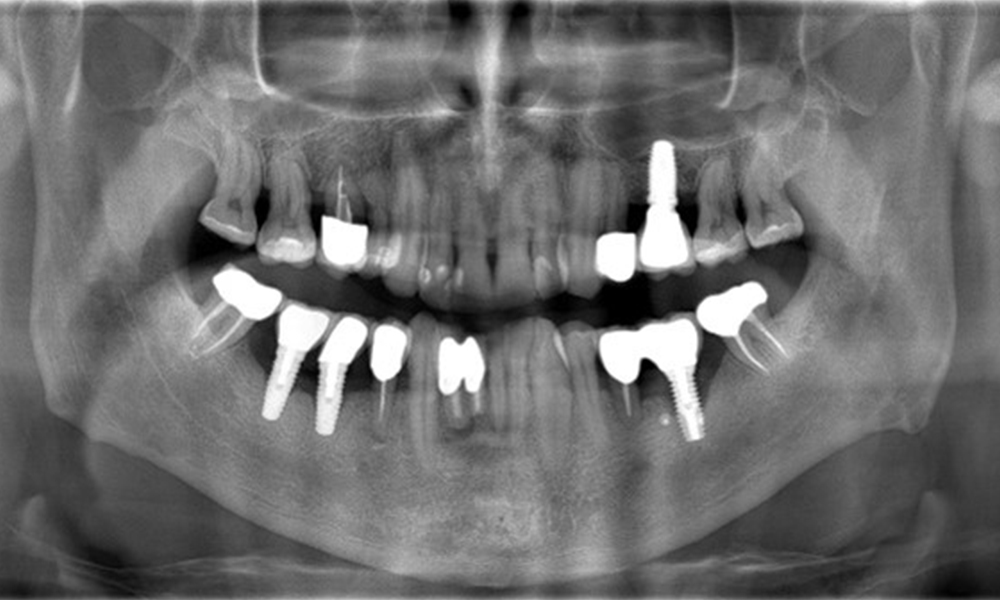

A 52-year-old patient presents at a preventive care session. The patient has no systemic disease and is not taking any medication. He has had various dental treatments and also has two active carious lesions. In addition, the patient has four implants (2nd, 3rd and 4th quadrants). He is revealed to have early periodontal disease (stage IV, grade B). His periodontal condition is stable; a probing depth of Probing depths (ST) of 5 mm is only evident at the implant in region 36. Gingivitis is also identified.

Previous treatments: multiple ceramic restorations, four implants (2nd, 3rd, 4th quadrants)

The X-ray images show the progression of bone loss. OPG from 29.06.2020 (left) and OPG from 26.02.2024 (right).

OPG: 26/02/2024 Dental X-ray: 18/01/2024